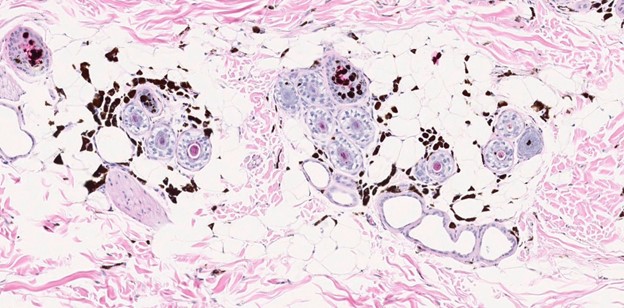

Figure 4. H&E, 2x magnification.

Figure 5. H&E, 10x & 20x magnification